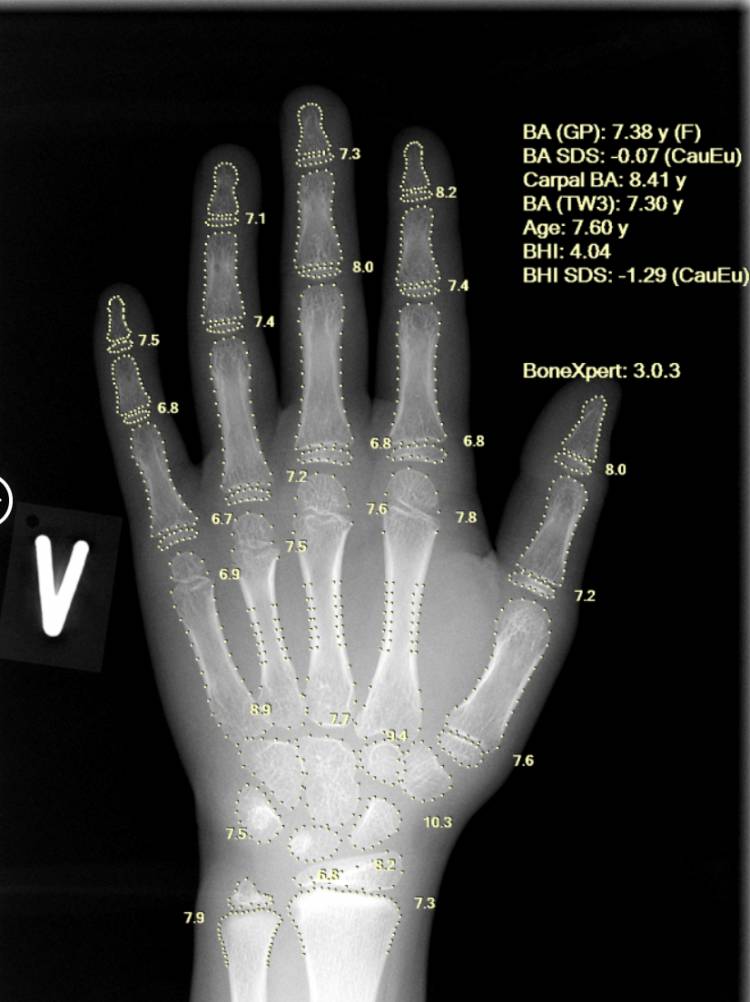

Using a single left-hand X-ray, BoneXpert provides a comprehensive, multi-method assessment, including Greulich-Pyle (GP) bone age, Tanner-Whitehouse (TW2/TW3) bone age, carpal bone age, as well as Bone Age SDS and Bone Health Index (BHI). This depth of analysis enhances diagnostic confidence and supports clinicians in early identification of constitutional growth delay and endocrine abnormalities at an early stage.

Developed by a Europe-based AI med-tech company and CE-approved, BoneXpert is considered a gold-standard solution for automated bone age assessment. The technology enables objective, accurate, and highly reproducible bone age analysis, eliminating inter- and intra-observer variability and ensuring consistent results from the same X-ray every time.